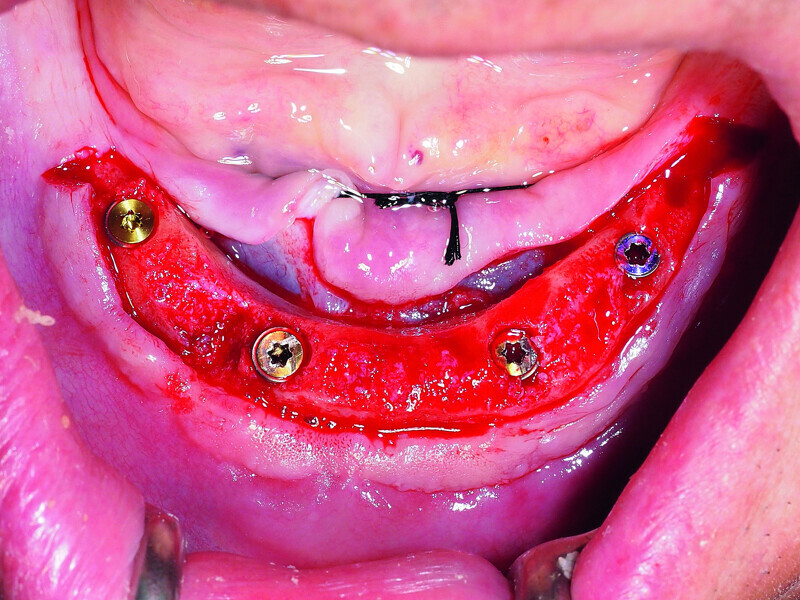

Fig. 2: Placement of four GC Aadva implants in the interforaminal region.